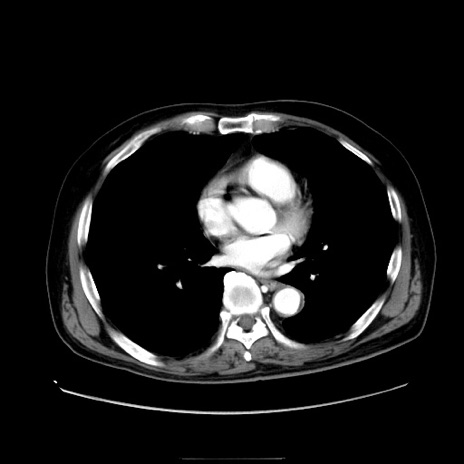

冠状断像

【症例】80歳代男性

【現病歴】約6時間前から臍下部痛が出現。次第に腹部膨隆・背部痛も生じてきたため来院。背部痛の場所は変化しない。

【身体所見】意識清明、BT 36.3℃、BP  131/87mmHg、P 87bpm、SpO2 100%(RA)、臍周囲自発痛・圧痛あり、反跳痛なし、自発痛部位に一致して板状硬あり、腹部膨隆、腸雑音減弱、CVA tenderness両側陰性。